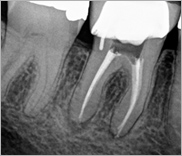

Υπολογιστική Τομογραφία Κωνικής Δέσμης CBCT

Η Υπολογιστική Τομογραφία Κωνικής Δέσμης (ΥΤΚΔ-CBCT) αποτελεί την πιο σύγχρονη απεικονιστική μέθοδο σκληρών μορίων (οστού και δοντιών) στην οδοντιατρική